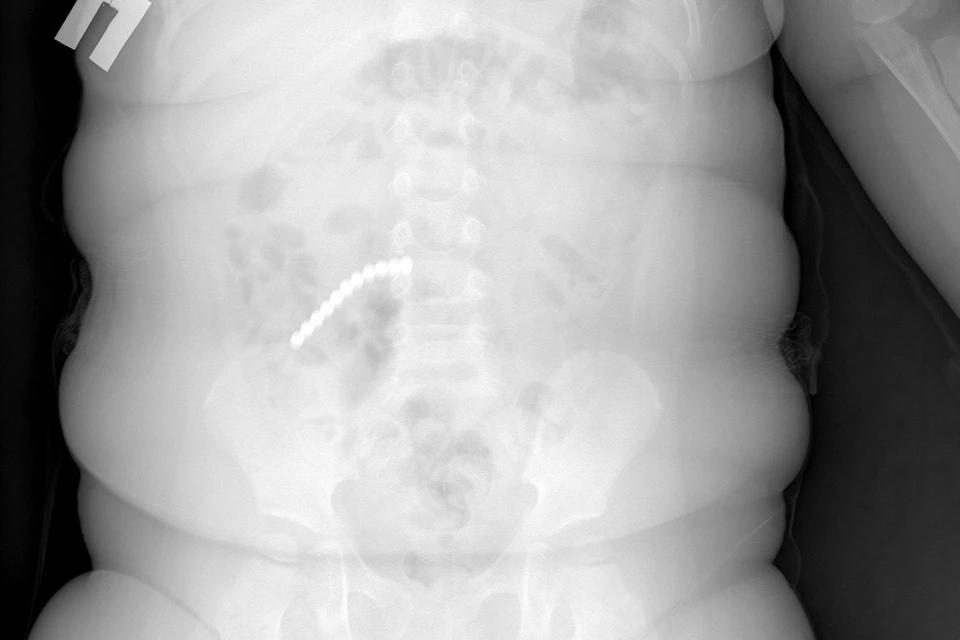

Двухлетний ребенок поступил в больницу с сильной рвотой и вялостью. Сначала родители думали - отравление или вирус. Но когда сделали рентген, врачи увидели страшное. Почти весь кишечник был усеян мелкими шариками. Как выяснилось, пациент проглотил 20 шариков от магнитного конструктора - неокуба.

Девять деталей врачам удалось достать через эндоскоп. Но основная проблема была впереди. Остальные магниты разошлись по кишечнику и начали притягиваться друг к другу через стенки кишок. Из-за этого петли тонкой, слепой и сигмовидной кишки буквально слиплись между собой. Началось воспаление, образовались дырки - перфорации.

- Магниты спрессовали кишки, возникли свищи. Часть шариков даже попала в аппендикс. Пришлось удалять и его тоже, - рассказал хирург Вячеслав Данчинов.

Ребенка пришлось экстренно оперировать. Хирурги убрали поврежденный участок тонкой кишки, ушили свищи. Операция была сложной, малыш несколько дней провел в реанимации. Сейчас его уже перевели в обычную палату - идет на поправку.

Врачи Детской республиканской клинической больницы бьют тревогу. Неокубы - не игрушка, а мина замедленного действия. Если шариков несколько, они могут «найти» друг друга внутри тела. Рентген такие магниты видит хорошо, но операция все равно неизбежна. А если промедлить - возможен летальный исход.